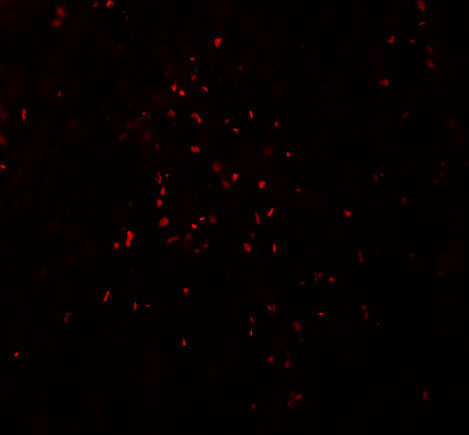

Immunofluorescence of ZBTB7A in human ovary tissue with ZBTB7A antibody at 20 μg/mL. |